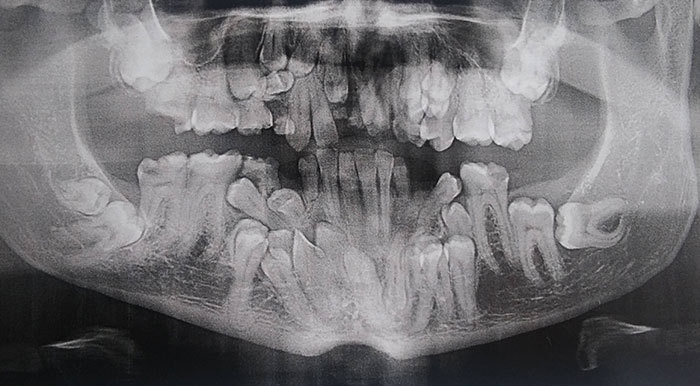

Подборка рентгеновских снимков, которые наглядно показывают, что от нас скрывает природа

Самые занимательные рентгеновские снимки, показывающие, что скрыто от глаз человека

Сегодня открытие немца используют во многих сферах жизни, начиная с медицины и заканчивая таможней. Собрали для вас самые занимательные рентгеновские снимки, показывающие, что скрыто от глаз человека.